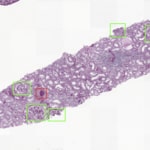

Avec 850 millions de personnes dans le monde entier souffrant de maladies rénales (1) et l’insuffisance rénale chronique (IRC) qui devrait devenir la cinquième cause de décès d’ici 2040(2), il existe un besoin urgent d’améliorer le diagnostic et le traitement. La suite rénale d’IA d’Aiosyn utilise des algorithmes de pathologie computationnelle alimentés par l’IA pour quantifier objectivement les scores des lésions rénales, offrant ainsi la possibilité d’améliorer la reproductibilité et d’accélérer le développement de médicaments. La plateforme résout le problème des limites de la classification de Banff actuellement utilisée dans l’analyse des biopsies rénales, qui subit la variabilité des observateurs et repose sur des évaluations qualitatives.

La suite rénale d’IA d’Aiosyn facilite l’identification et la caractérisation des processus pathologiques, et ouvre une voie prometteuse à d’importantes améliorations dans la recherche et les essais cliniques sur l’insuffisance rénale chronique. Parallèlement à sa plateforme d’IA rénale, Aiosyn développe activement des algorithmes avancés d’apprentissage approfondi visant à la détection de biomarqueurs du cancer.